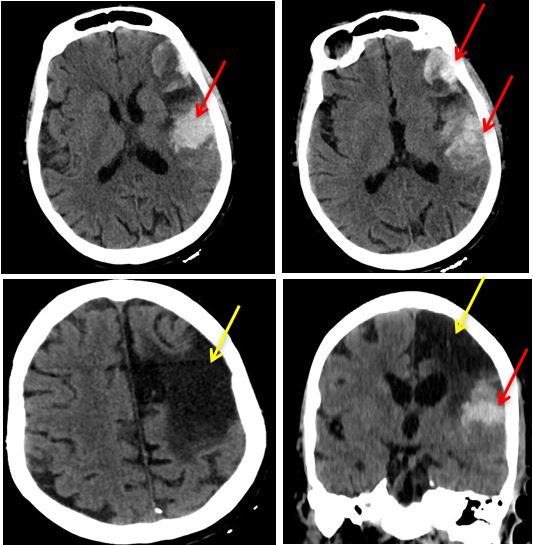

Fig. 1. Computed tomography of brachiocephalic arteries and the brain of the patient before surgical intervention (2020): cystogliotic alterations of the left frontal lobe (A); occlusion of the common carotid artery (B).

On the 2nd day after the operation, the patient had an episode of extended headache of high intensity, psychomotor excitement, buildup of the previously existing neurological deficit (aggravation of right-sided paresis to 2 points, the appearance of total aphasia), an episode of partial tonic seizures in the right (paretic) limbs (eliminated by diazepam 10 mg intravenously in the RICU). Arterial pressure in the lower limbs was 170/80 mm Hg. An emergency CT scan of the brain showed a picture of fresh hemorrhage into the area of cystic post-ischemic alterations in the left parietal zone (Figure 7). The authors believe that, probably, the initial rise in the arterial pressure in this patient after the first and second operations was induced by direct intervention on the carotid arteries.

Fig. 7. Computed tomography of the brain with the underlying progression of neurological symptoms: hemorrhage into the area of ischemic alterations after past acute cerebrovascular event in 2005. Notes: in red, fresh acute cerebrovascular event of hemorrhagic type is shown, in yellow — old ischemic focus.